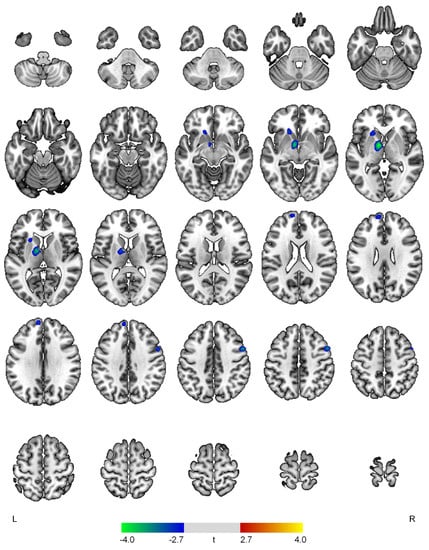

| Positive correlations with the affective domain | ||||

| None | ||||

| Negative correlations with the affective domain | ||||

| L thalamus | 4.08 | <0.001 | 427 | −8, −2, −2 |

| R precentral gyrus | 3.59 | <0.001 | 172 | 54, 8, 42 |

| L superior frontal gyrus | 3.06 | 0.002 | 160 | −8, 56, 30 |

| L caudate | 3.05 | 0.002 | 165 | −18, 22, −4 |